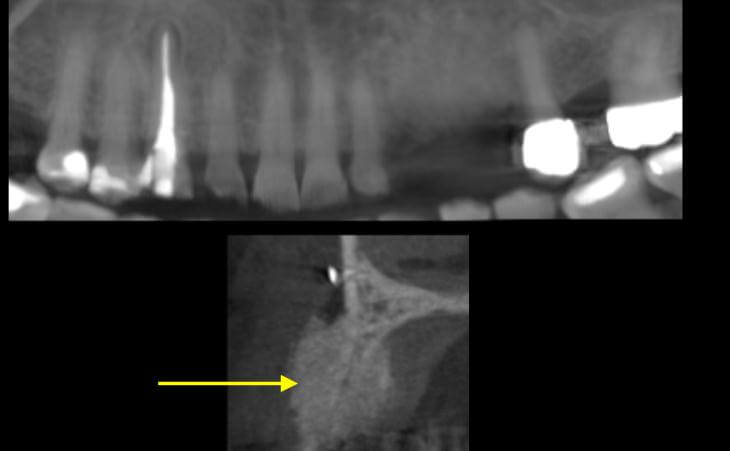

This 19 year old female was born with missing lateral teeth #7 and #10. She had a very resorbed bony areas in her upper jaw where the missing teeth were supposed to be. A CT scan was done. Then a bone regeneration graft was placed and 4 months of healing went by. A New Ct scan was taken to plan the implant placement. Implants were placed into the newly formed bone successfully.